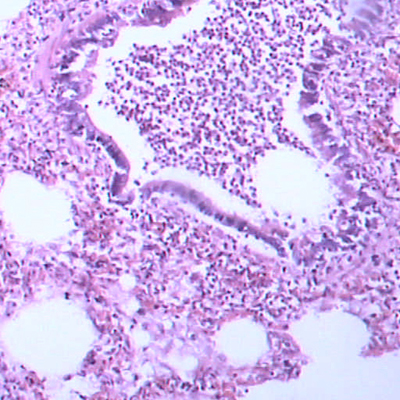

腺病毒主要感染儿童,大多无症状。相关的临床病症主要是小儿急性咽炎、急性呼吸道感染和病毒性肺炎等。 某些型别腺病毒可引起婴儿腹泻,称肠道腺病毒。此外,还能导致其它一些临床疾病,如小儿的急性出血性膀胱炎。

其中腺病毒肺炎是我国北方儿童的一种常见病,1958年曾有过大流行。A组腺病毒在体外具有转化细胞的性质,并能对新生地鼠致癌。但迄今尚未见在人体致癌的报告。